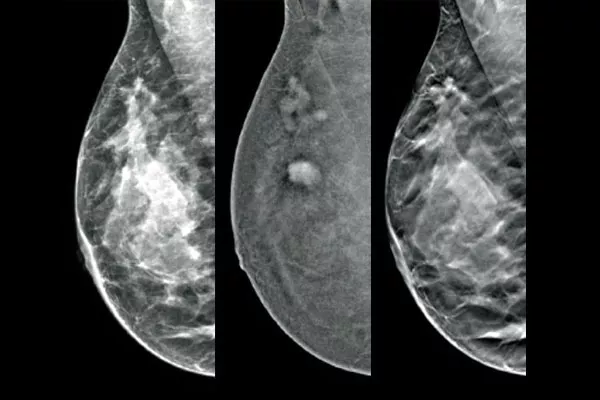

Target and biopsy lesions identified with 2D contrast-enhanced mammography through a stereotactic-based procedure, with a comparable diagnostic performance to a breast MRI procedure.1,2 Compare post-marker images in the same modality as the initial diagnostic contrast exam.

Affirm Contrast Biopsy software allows you to biopsy lesions identified during the I-View® contrast-enhanced 2D mammogram. By leveraging the ability to provide 2D, contrast-enhanced, and tomosynthesis images under one compression,4 The Affirm Upright Breast Biopsy Guidance System enables a quick transition from screening to biopsy, leveraging the same proven imaging chain5 as the mammography system to improve 3D™ visualisation of suspicious lesions.**

Functional imaging, using CEM, compares favourably to breast MRI with similar sensitivity, higher specificity, and higher positive predictive value.7,8 In addition, CEM provides a cost-effective diagnostic imaging alternative9 compared to MRI, with a shorter procedural time.7,10